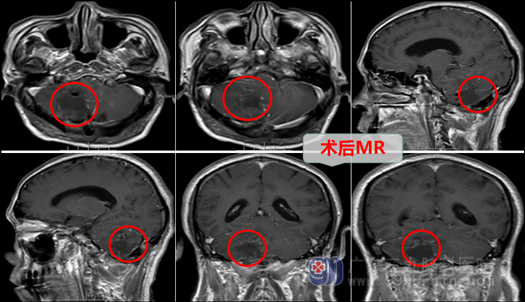

秦某还算幸运,他入住外十科后,欧阳辉教授带领团队,迅速给他明确了诊断,并及时安排了治疗。患者在全麻下行右侧小脑脓肿切除术。术中穿刺小脑深约1.5cm见白色脓液,抽吸出约15ml左右脓液后,脑组织塌陷,所抽取脓液送检验科检验。检验科发现:细菌(+),革兰氏阴性杆菌和革兰氏阳性球菌。显微镜下保护好脑组织,注意防止脓肿扩散,沿脓肿周边水肿脑组织仔细分离脓肿壁,切除全部脓肿壁,将脓肿完全切除,患者脑积水也随之缓解。术毕,手术顺利。

术后,患者生命征平稳,神志清醒,应用针对性的抗菌药物等治疗。一周后,秦某头部切口愈合好,继续给以抗感染、神经营养、支持对症治疗,2022-5-5,秦某顺利出院,其全家都非常高兴,因为他终于逃过了凶恶的死神—脑脓肿。